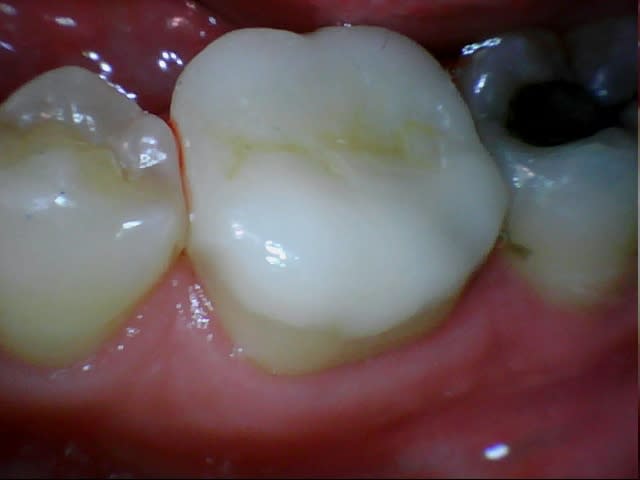

29/11/2011 à 19h22

Assez nase l'onlay Emax en couleur (B2.5 demandée, les deux teintes à côté B2 et B3), en sculpture mais là je suis responsable, j'aurais dû ménager plus de place.

J'ai etché silané mais aurais-je dû ? J'ai pris du G-Cem, j'ignore si c'est aussi efficace qu'en collage classique.

J'ai posé une digue sur la seule dent, erreur car avec l'épaisseur de la feuille, ça passe plus en proximal, donc j'ai maintenu l'élément encollé au pouce, retiré tout le tintouin en vitesse et retrouvé un torrent salivaire menaçant.

À la réflexion à froid j'aurais dû donner deux coups de ciseau/scalpel sur la digue en proximal, ç'aurait été mieux en dépannage.

Je ne sais pas encore quelle compo auto prendre pour les collages, la teinte a probablement été altérée par le G-Cem. Il y a le classique Variolink pratique avec ses seringues à produit hydrosoluble pour essai esthétique mais est-ce le meilleur produit ?

Il n'y aurait pas eu une languette profonde en distal j'aurais pris un compo photo et insolé au travers de l'onlay.